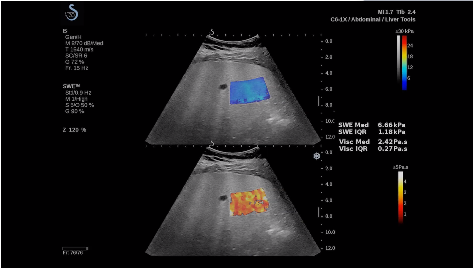

法國(guó)聲科影像(SuperSonic Imagine,SSI. Euroniex:FR0010526814)近日發(fā)表公告,宣布其研發(fā)的新一代“極速”超聲成像平臺(tái)(UltraFast Imaging),首次實(shí)現(xiàn)了肝臟的多項(xiàng)超聲定量評(píng)估新指標(biāo)同步檢測(cè),包括:Att PLUS,SSp PLUS和Vi PLUS等,基本涵蓋肝臟相關(guān)病理變化指征的如纖維化、脂肪變、炎癥等。據(jù)悉,此多項(xiàng)新技術(shù)新將搭載于新Aixplorer系列E超系統(tǒng)。

法國(guó)聲科影像公司(SuperSonic Imagine. SA,F(xiàn)rance),2005年由三位諾貝爾獎(jiǎng)級(jí)科學(xué)家主導(dǎo)創(chuàng)立,專(zhuān)注于E超的開(kāi)發(fā)和生產(chǎn),是目前世界上唯一可以同時(shí)應(yīng)用兩種波進(jìn)行人體檢測(cè)的系統(tǒng):縱波形成高質(zhì)量的二維組織結(jié)構(gòu)圖像,而橫波可以使醫(yī)生實(shí)時(shí)準(zhǔn)確地看到并分析組織的硬度,有效減少有創(chuàng)檢查、避免損傷。

E超是在原有B超、彩超(彩色多普勒CDFI)基礎(chǔ)上研發(fā)成功的新一代超聲剪切波彈性成像系統(tǒng),是一種能夠全面應(yīng)用于表淺組織、腹部臟器,血管等方面的組織彈性成像技術(shù)。根據(jù)組織硬度彈性值的不同,有效鑒別實(shí)性腫瘤的良惡性。對(duì)于惡性病變的診斷具有較高的特異性和敏感性,尤其對(duì)于甲狀腺、乳腺、前列腺等小器官,能夠完成常規(guī)超聲不能完成的組織定量分析,可以實(shí)時(shí)、全幅、全定量獲得組織彈性(硬度)信息,為鑒別腫瘤的良惡性提供客觀(guān)、量化的診斷依據(jù)。